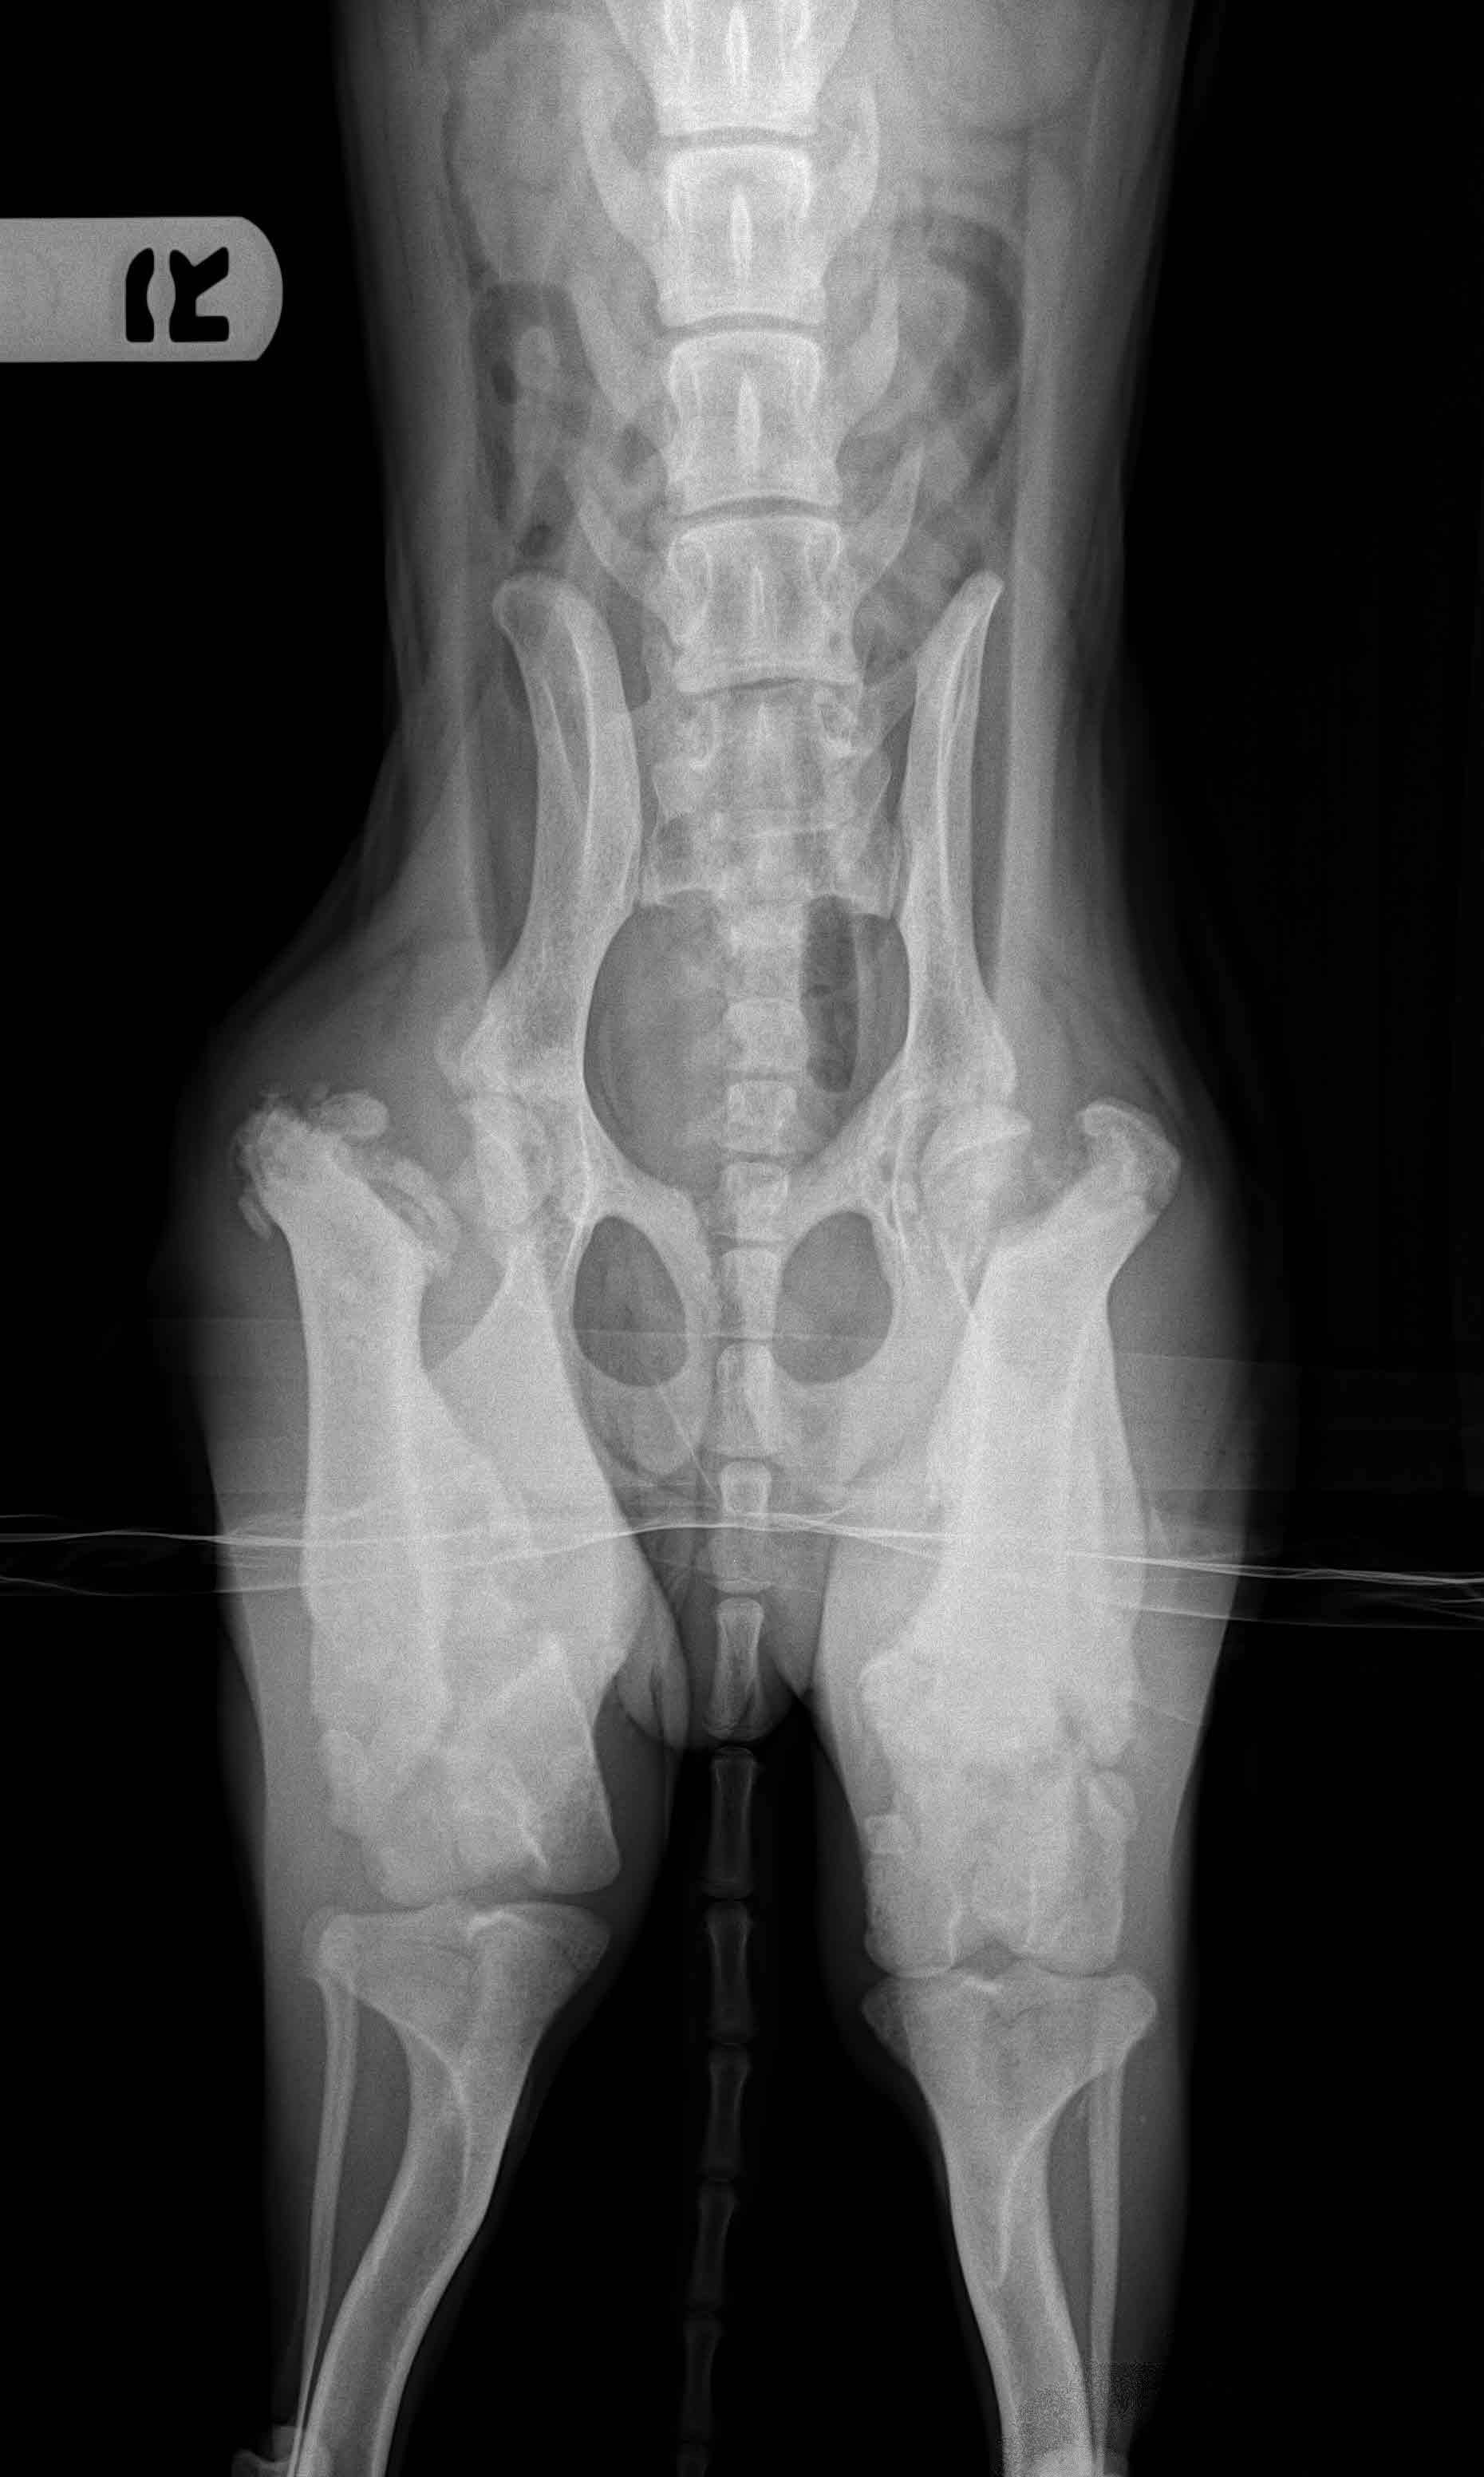

Sweet JELLY BEAN has found her FOREVER HOME.

It's been six months. Jelly Bean has had corrective surgery on her back legs. She's had lots of rehabilitation. She is now a healthy and happy girl who loves life!